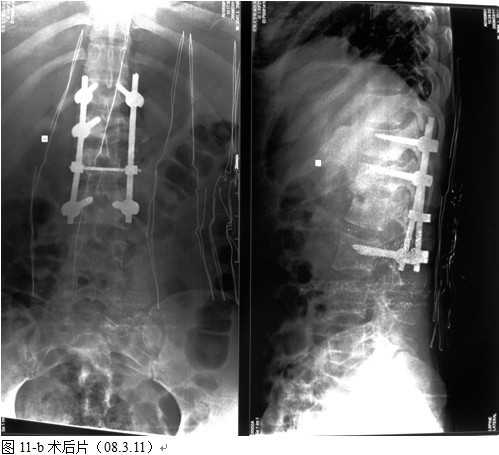

图11-a术前

以病变椎体为中心,作一后正中切口,显露病椎棘突、椎板、关节突以及上下需要固定的正常椎体,根据后凸畸形的严重程度在C 型臂协助下确定进钉角度和方向,置入椎弓根钉,椎弓根钉固定的方法:病灶上下相邻正常椎体置入,当病椎骨质破坏不超过1/3或未累计椎弓根时置入相对较短的钉子,一般长度为35mm,当骶1椎体有破坏时,根据骨质的情况确定入钉的方向,将病椎上、下关节突关节切除,自椎间孔显露病灶,直视神经根状态下进行病灶清除和椎管减压,可将干酪样物,死骨,坏死的椎间盘大部分清除,解除硬膜囊的压迫,必要者可双侧同时病灶清除,减压。无钛棒状态下用椎体撑开器轻柔牵开,采用前路撑开结合后路固定维持有限撑开或加压缓慢矫正脊柱后凸畸形,特别注意是由于结核患者骨质疏松,不可用钉棒大力撑开,否则钉子拔出可能性较大。要前路撑开加后路加压来达到矫形的目的。撑开后,缺损空间增大,大部分用手指可触及缺损内的情况,能进一步彻底清除病灶及对侧的病灶,反复用异烟肼盐水混合液冲洗病灶,凿出植骨床,植骨时需注意植骨块要采用“平进竖植”方法,循序用植骨打入器和辅助器械缓慢植入否则易导致神经根损害。植骨完成后再次采用内固定适当加压促使骨块稳定及融合,如果病灶中的脓液稀薄较多时,在病灶中留置一根硬膜外管,术后注射异烟肼,每周两次,以提高局部的药物浓度,在对侧椎板,关节突间植骨,病灶内留置链霉素2.0g ,放置引流管,闭合伤口。

术后卧床2 周后,配戴支具下床活动。支具配戴时间3~4 个月,术后继续四联抗痨药物治疗,吡嗪酰胺应用3 个月后停药,3个月定期复查肝功,血沉,C-反应蛋白及X线片,同时口服保肝药物 ,持续治疗9~12个月。